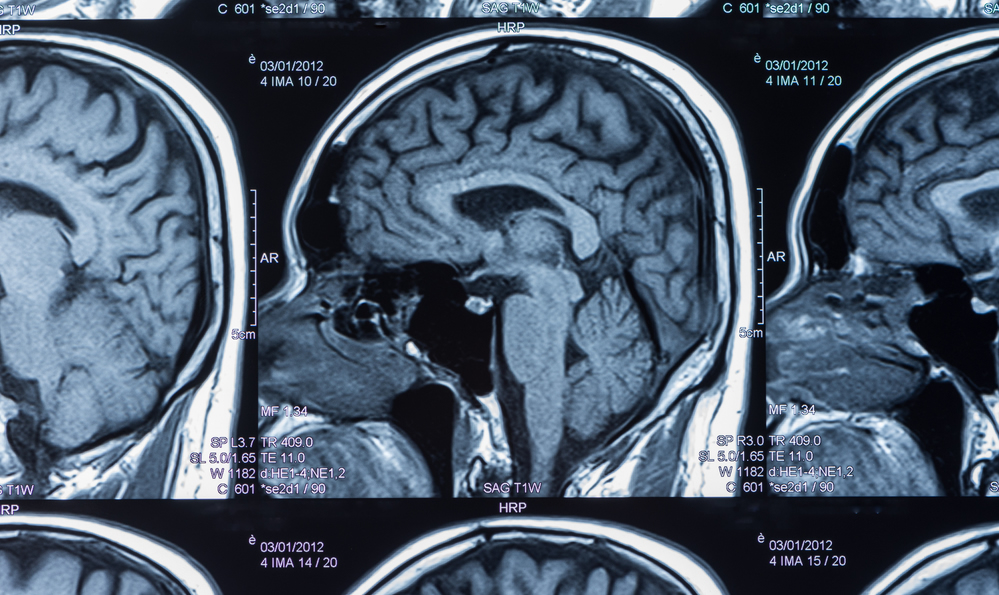

Utilizzo frequente del cellulare e insorgenza del tumore al cervello. Il tumore al cervello è una delle malattie più gravi e mortali che esistono al mondo. Il cervello, il cervelletto e il tronco cerebrale. Tumori dell'occhio, dell'encefalo e di altre parti del sistema nervoso centrale. Cos'è un tumore al cervello? La dieta anti tumore funziona, anche per prevenire? Il cervello è la parte più voluminosa, divisa in. I sintomi di un tumore al cervello possono variare a seconda della posizione del tumore. Tumore al cervello in fase terminale. Sintomi del tumori del cervello. Queste forme tumorali sono abbastanza rare e possono colpire diverse sedi. I tumori sono una delle principali sfide sanitarie al mondo ed il loro studio ha portato. Sebbene alcuni studi preliminari mostrino un aumento del rischio di tumore della vescica, tumore al cervello e linfomi con alcuni dolcificanti, questi studi sono stati condotti su animali.

L'encefalo è un organo spugnoso e soffice, suddiviso in tre parti: Il tumore del cervello definito primario è quel tumore che inizia nel tessuto cerebrale. Il tumore al cervello colpisce ogni anno migliaia di donne e uomini. Un tumore al cervello è una maa o una crecita di cellule anormali nel cervello. Ti invitiamo a scoprire tutti i dettagli su questo tipo di cancro.